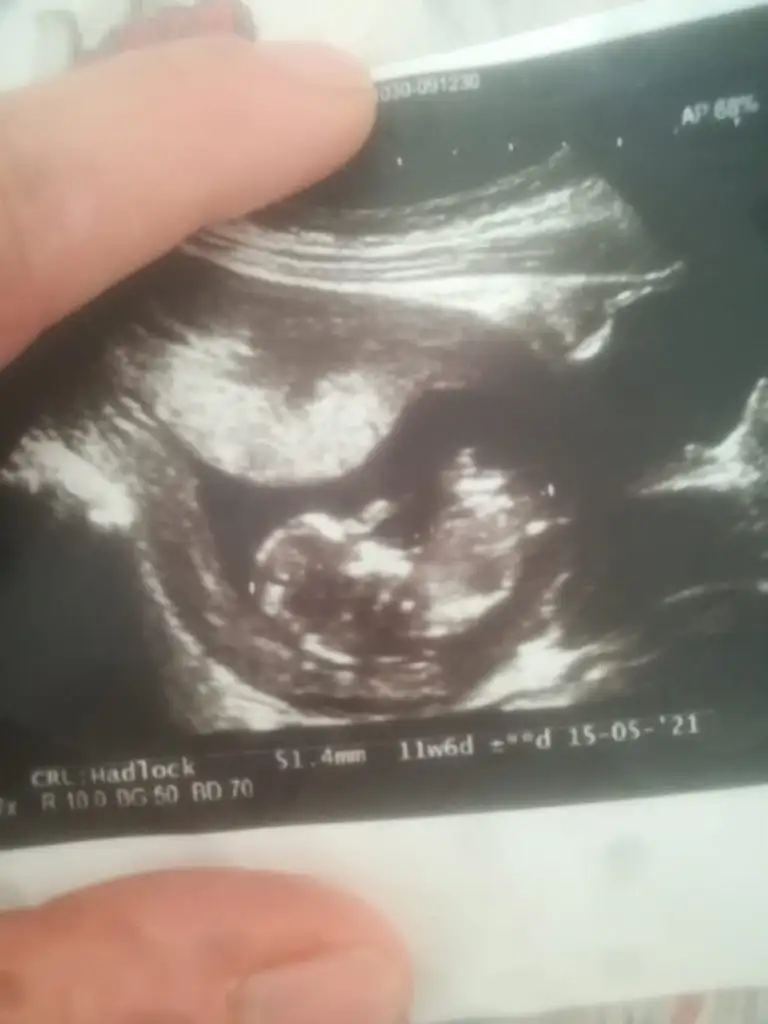

Bu 11 haftalık:)Orası çok minik nasıl tahmin ederim ki 11 12 13 haftalar olursa paylaşın

Yok USG minik hiç birşey görünmüyorBu 11 haftalık:)

Tamam cnm teşekkür ederim ben başka biriyle kariştirdim size haftaya paylaşirim çok teşekkür ederimDün yazdım ya kiza benziyor 12-13 haftayida paylaşın sonra gelip kız dediniz demeyin diye

Net değil usg11 haftalik ikra meyra hanim tahmin alabilirmiyiz